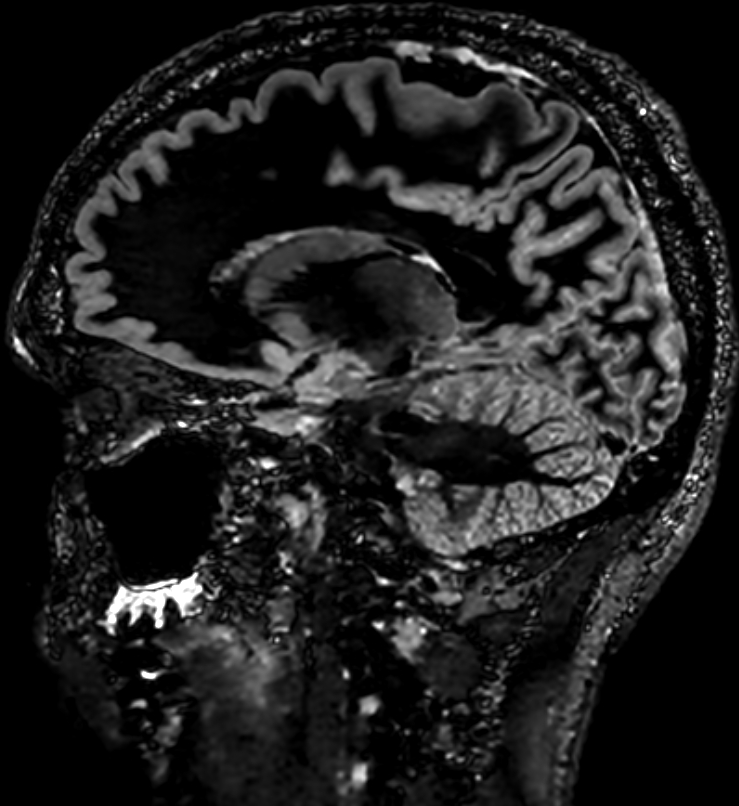

Unveiled at RSNA 2024, Sonic DL for 3D[v] is a deep learning innovation designed to reduce MRI scan times by up to 86%. Following the launch of Sonic DL for cardiac imaging, this extension to 3D is expected to offer enhanced resolution for brain, spine, orthopedic, and body imaging – while retaining the same impressive scanning speed of up to 12 times acceleration. For neurology, Sonic DL for 3D is designed to enable high-resolution imaging of complex brain structures, allowing for quicker, clearer insights into neurological conditions.